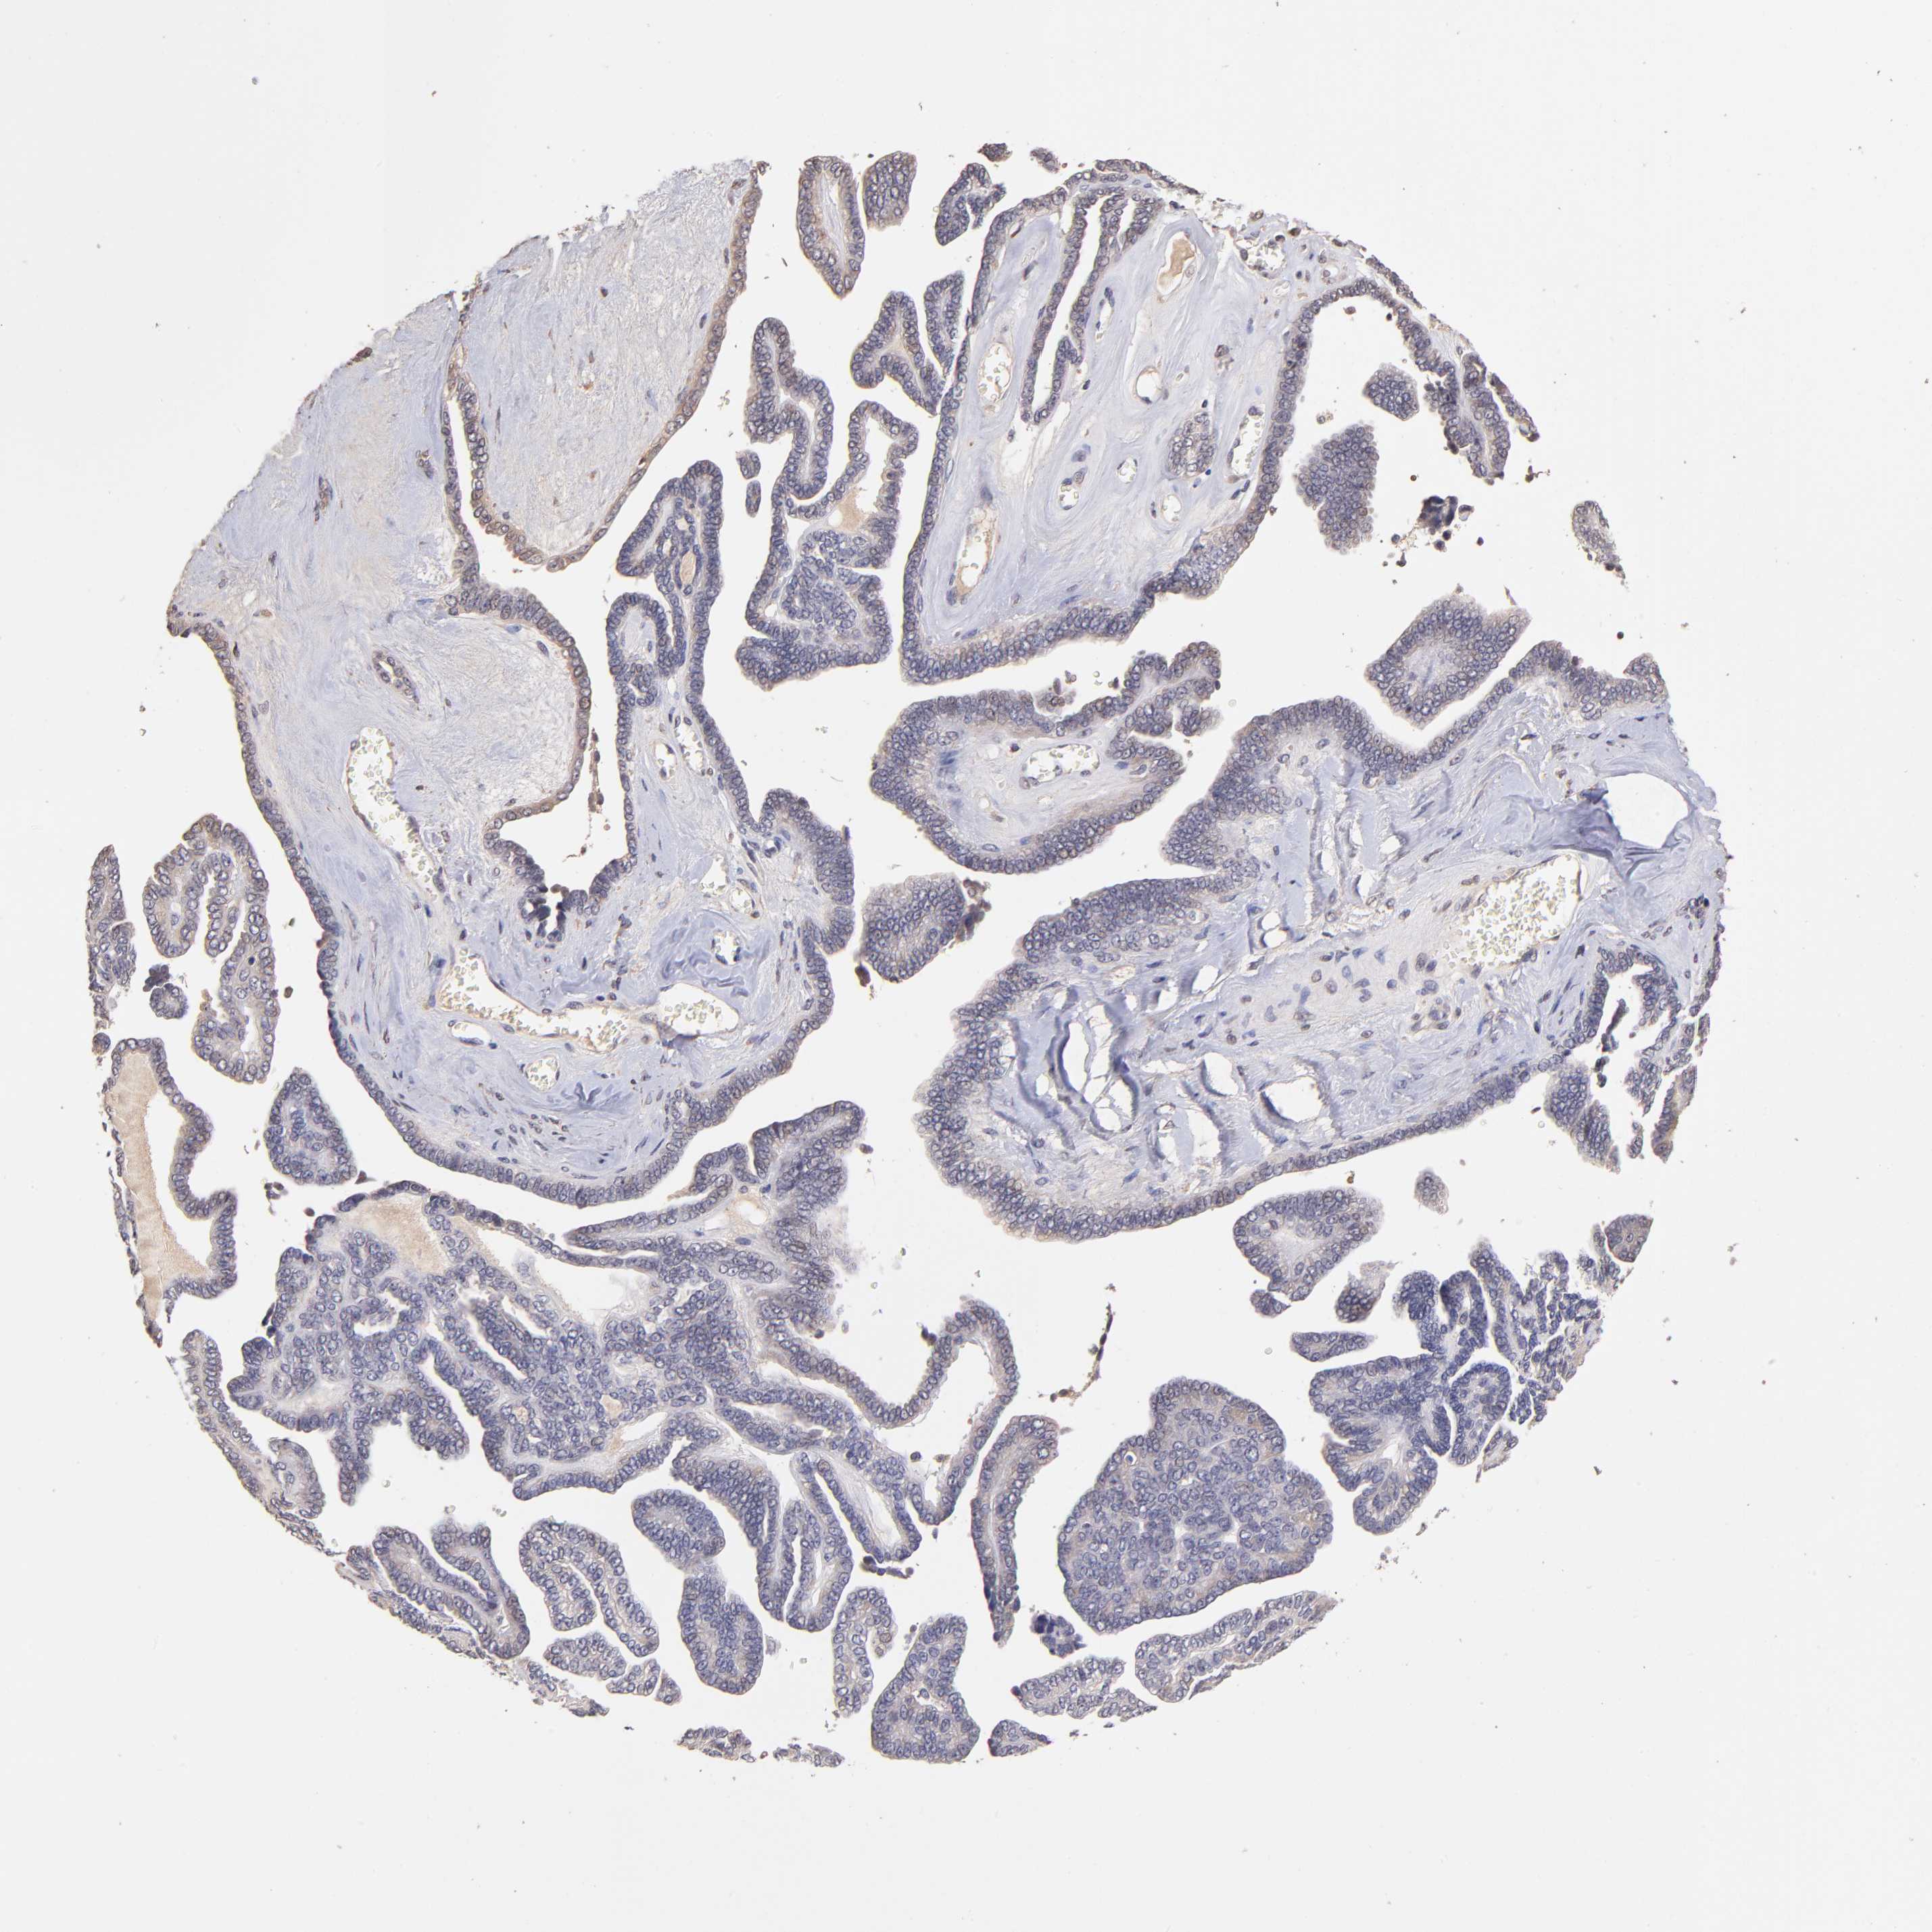

OVARIAN CANCER - Protein expressioni

A mouse-over function shows sample information and annotation data. Click on an image to view it in a full screen mode. Samples can be filtered based on level of antibody staining by selecting one or several of the following categories: high, medium, low and not detected. The assay and annotation is described here.

Note that samples used for immunohistochemistry by the Human Protein Atlas do not correspond to samples in the TCGA dataset.

Antibody stainingi

Antibody staining in the annotated cell types in the current human tissue is reported as not detected, low, medium, or high, based on conventional immunohistochemistry profiling in selected tissues. This score is based on the combination of the staining intensity and fraction of stained cells.

Each image is clickable and will lead to virtual microscopy that enables deeper exploration of all samples and also displays staining intensity scores, fraction scores and subcellular localization as well as patient and tissue information for each sample.

Antibody HPA002633

Antibody HPA046758

Antibody CAB010906

Carcinoma, endometroid

Cystadenocarcinoma, serous, NOS

Cystadenocarcinoma, mucinous, NOS

Carcinoma, NOS